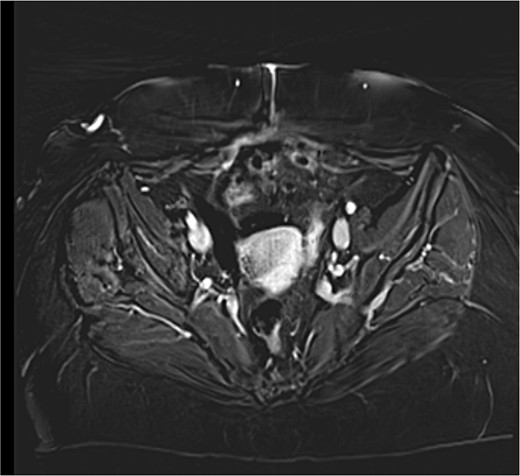

The patient underwent an MRI which revealed a large cystic pelvic mass, measuring 10.3 x 9 x 11.1 cm, with septations and solid component in contact with the anterior abdominal wall, and the bladder as well (Fig. 1). There was no evidence of vascular invasion from the mass. A colonoscopy followed in order to exclude the involvement of the colon and rectum, which was normal.

MRI T2 axial (A) and sagittal (B): solitary mass in contact with rectus abdominis.